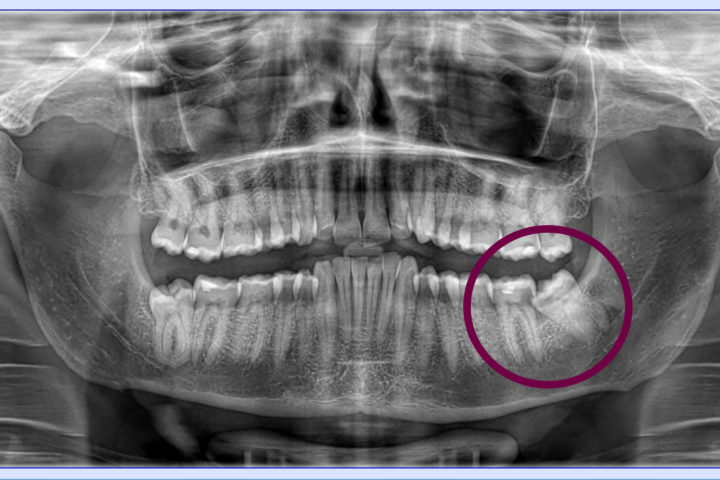

Diagnosi con TAC Cone Beam

Grazie alla tecnologia Cone Beam 3D, l’estrazione dei denti del giudizio e delle radici dentali fratturate viene pianificata con la massima precisione, valutando posizione, profondità e rapporti con le strutture anatomiche vicine.